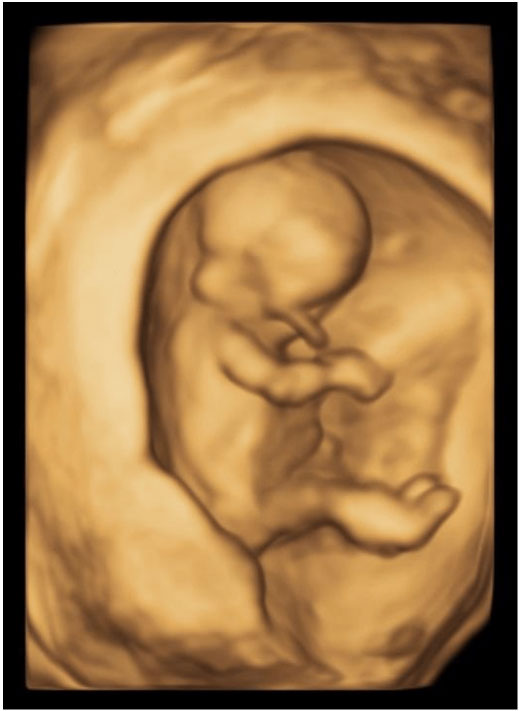

The first trimester ultrasound is performed between 11+ 0-13 + 6 weeks. This is an ideal time to assess the baby to exclude certain major abnormalities. The baby is well formed at this stage so we can examine the baby’s head, face, abdomen, stomach, legs and arms. At Western Imaging for Women, we will also examine the heart, as it is sometimes possible to identify major heart problems at this very early stage, even though the size of the baby’s heart is still very small.

If possible, we try to obtain some 3D / 4D pictures of your baby. This allows you to see your baby and provides a great opportunity for you to bond with your unborn baby.